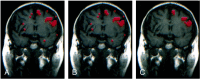

Background and purpose: Functional MR (fMR) imaging of word generation has been used to map Broca's area in some patients selected for craniotomy. The purpose of this study was to measure the reliability, precision, and accuracy of word-generation tasks to identify Broca's area.

Methods: The Brodmann areas activated during performance of word-generation tasks were tabulated in 34 consecutive patients referred for fMR imaging mapping of language areas. In patients performing two iterations of the letter word-generation tasks, test-retest reliability was quantified by using the concurrence ratio (CR), or the number of voxels activated by each iteration in proportion to the average number of voxels activated from both iterations of the task. Among patients who also underwent category or antonym word generation or both, the similarity of the activation from each task was assessed with the CR. In patients who underwent electrocortical stimulation (ECS) mapping of speech function during craniotomy while awake, the sites with speech function were compared with the locations of activation found during fMR imaging of word generation.

Results: In 31 of 34 patients, activation was identified in the inferior frontal gyri or middle frontal gyri or both in Brodmann areas 9, 44, 45, or 46, unilaterally or bilaterally, with one or more of the tasks. Activation was noted in the same gyri when the patient performed a second iteration of the letter word-generation task or second task. The CR for pixel precision in a single section averaged 49%. In patients who underwent craniotomy while awake, speech areas located with ECS coincided with areas of the brain activated during a word-generation task.

Conclusion: fMR imaging with word-generation tasks produces technically satisfactory maps of Broca's area, which localize the area accurately and reliably.